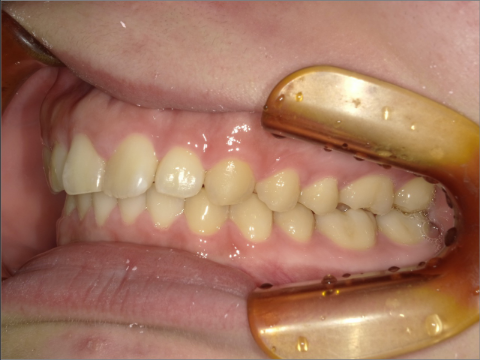

ご年齢 35歳男性 治療期間 2022/08/22〜2023/03/24(1年5ヶ月)

診断 110,000円(税込) アライナー 550,000円(税込) リテーナー 55,000円(税込)

ご年齢 35歳男性

治療期間 2022/08/22〜2023/03/24(1年5ヶ月)

診断 110,000円(税込)

アライナー 550,000円(税込)

リテーナー 55,000円(税込)

BEFORE

AFTER